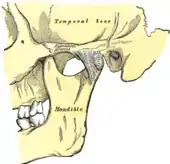

Anatomy and physiology

Temporomandibular joints

The temporomandibular joints are the dual articulation of the mandible with the skull. Each TMJ is classed as a "ginglymoarthrodial" joint since it is both a ginglymus (hinging joint) and an arthrodial (sliding) joint,[41] and involves the condylar process of the mandible below, and the articular fossa (or glenoid fossa) of the temporal bone above. Between these articular surfaces is the articular disc (or meniscus), which is a biconcave, transversely oval disc composed of dense fibrous connective tissue. Each TMJ is covered by a fibrous capsule. There are tight fibers connecting the mandible to the disc, and loose fibers which connect the disc to the temporal bone, meaning there are in effect 2 joint capsules, creating an upper joint space and a lower joint space, with the articular disc in between. The synovial membrane of the TMJ lines the inside of the fibrous capsule apart from the articular surfaces and the disc. This membrane secretes synovial fluid, which is both a lubricant to fill the joint spaces, and a means to convey nutrients to the tissues inside the joint. Behind the disc is loose vascular tissue termed the "bilaminar region" which serves as a posterior attachment for the disc and also fills with blood to fill the space created when the head of the condyle translates down the articular eminence.[42] Due to its concave shape, sometimes the articular disc is described as having an anterior band, intermediate zone and a posterior band.[43] When the mouth is opened, the initial movement of the mandibular condyle is rotational, and this involves mainly the lower joint space, and when the mouth is opened further, the movement of the condyle is translational, involving mainly the upper joint space.[44] This translation movement is achieved by the condylar head sliding down the articular eminence, which constitutes the front border of the articular fossa.[35] The function of the articular eminence is to limit the forwards movement of the condyle.[35] The ligament directly associated with the TMJ is the temporomandibular ligament, also termed the lateral ligament, which really is a thickening of the lateral aspect of the fibrous capsule.[35] The stylomandibular ligament and the sphenomandibular ligament are not directly associated with the joint capsule. Together, these ligaments act to restrict the extreme movements of the joint.[45]